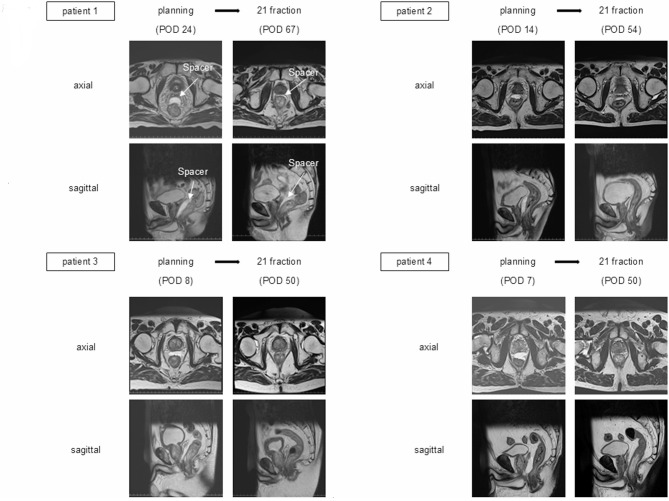

Methods: We included 103 patients implanted with hydrogel spacers who underwent proton therapy at our hospital between April 2020 and November 2022. Two patients were excluded due to improper hydrogel spacer placement beyond the prostatic side of Denonvilliers' fascia. To examine the volume of Space OAR, we measured the spacer volume using magnetic resonance imaging at the time of dosimetry treatment planning and again at 7 and 21 fractions in the remaining 101 patients.

Results: Among the 101 patients, four exhibited a significant reduction in spacer volume at 21 fractions, and one of these patients experienced rectal bleeding.

Conclusion: Unexpected early changes in the hydrogel spacer volume may increase rectal exposure from the time of radiation planning.